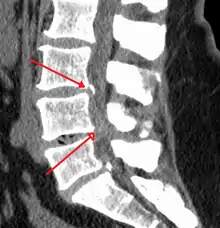

The diagnosis of spinal stenosis involves a complete evaluation of the spine. The process usually begins with a medical history and physical examination. X-ray and MRI scans are typically used to determine the extent and location of the nerve compression.

MRI

MRI has become the most frequently used study to diagnose spinal stenosis. The MRI uses electromagnetic signals to produce images of the spine. MRIs are helpful because they show more structures, including nerves, muscles, and ligaments, than seen on X-rays or CT scans. MRIs are helpful at showing exactly what is causing spinal nerve compression.